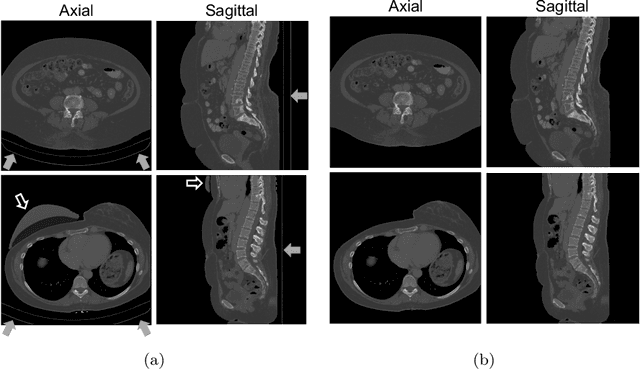

Abstract:High-grade serous ovarian carcinoma (HGSOC) is characterised by significant spatial and temporal heterogeneity, typically manifesting at an advanced metastatic stage. A major challenge in treating advanced HGSOC is effectively monitoring localised change in tumour burden across multiple sites during neoadjuvant chemotherapy (NACT) and predicting long-term pathological response and overall patient survival. In this work, we propose a self-supervised deformable image registration algorithm that utilises a general-purpose image encoder for image feature extraction to co-register contrast-enhanced computerised tomography scan images acquired before and after neoadjuvant chemotherapy. This approach addresses challenges posed by highly complex tumour deformations and longitudinal lesion matching during treatment. Localised tumour changes are calculated using the Jacobian determinant maps of the registration deformation at multiple disease sites and their macroscopic areas, including hypo-dense (i.e., cystic/necrotic), hyper-dense (i.e., calcified), and intermediate density (i.e., soft tissue) portions. A series of experiments is conducted to understand the role of a general-purpose image encoder and its application in quantifying change in tumour burden during neoadjuvant chemotherapy in HGSOC. This work is the first to demonstrate the feasibility of a self-supervised image registration approach in quantifying NACT-induced localised tumour changes across the whole disease burden of patients with complex multi-site HGSOC, which could be used as a potential marker for ovarian cancer patient's long-term pathological response and survival.

Abstract:This study investigates the use of the unsupervised deep learning framework VoxelMorph for deformable registration of longitudinal abdominopelvic CT images acquired in patients with bone metastases from breast cancer. The CT images were refined prior to registration by automatically removing the CT table and all other extra-corporeal components. To improve the learning capabilities of VoxelMorph when only a limited amount of training data is available, a novel incremental training strategy is proposed based on simulated deformations of consecutive CT images. In a 4-fold cross-validation scheme, the incremental training strategy achieved significantly better registration performance compared to training on a single volume. Although our deformable image registration method did not outperform iterative registration using NiftyReg (considered as a benchmark) in terms of registration quality, the registrations were approximately 300 times faster. This study showed the feasibility of deep learning based deformable registration of longitudinal abdominopelvic CT images via a novel incremental training strategy based on simulated deformations.